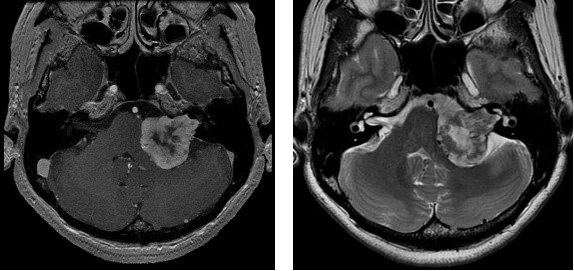

神経鞘腫のMRI

神経を包んでいる神経鞘(しんけいしょう)という組織から発生する、基本的に良性の腫瘍です。全身あらゆる神経に発生しますが、脳の中で最も多いのは聴神経です。この神経は更に、音を聞く蝸牛神経と体のバランスをとる前庭神経に分かれており、腫瘍は前庭神経から発生するため、聴神経腫瘍、聴神経鞘腫、前庭神経鞘腫などいろいろな呼び方がありますが、すべて同一のものです。

音の聞こえにくさ、耳鳴りが多く、他にはめまい、ふらつきもあります。この腫瘍では、水頭症という病気が合併することもあります。